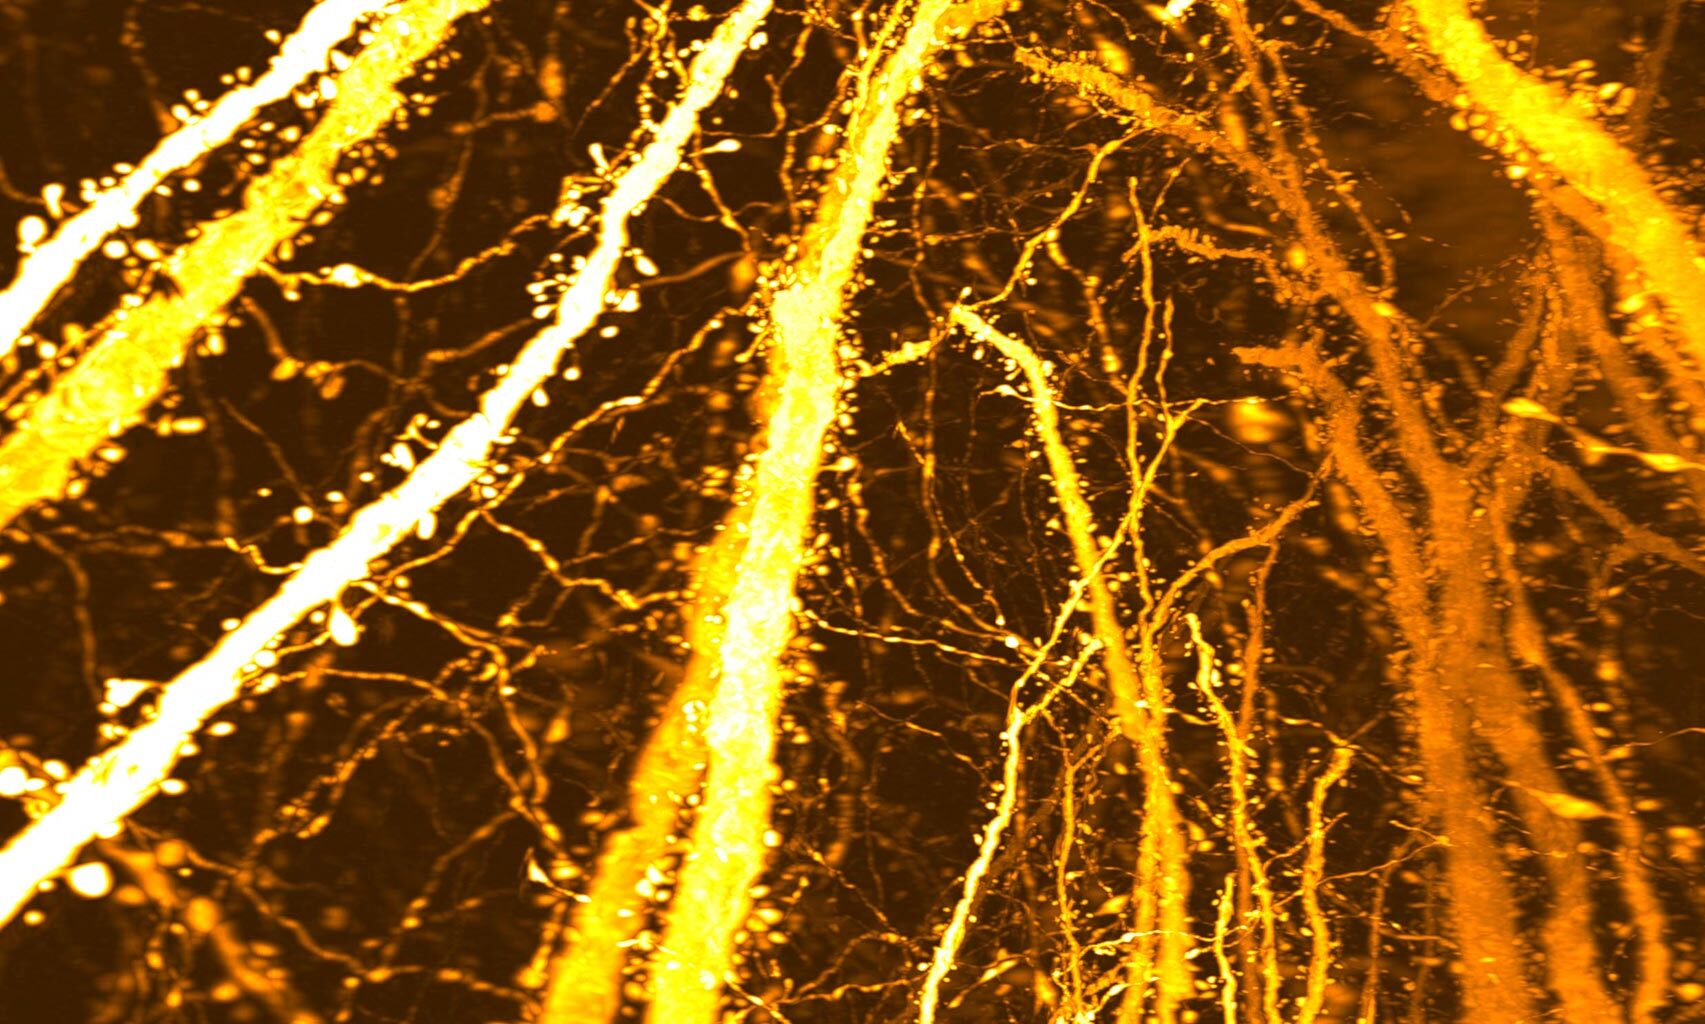

This image shows densely accumulated dendritic spines. Researchers from Kyushu University discovered a previously unrecognized synaptic “hotspot” that forms during adolescence, challenging the long-held view that adolescent brain development is driven mainly by synaptic pruning. Credit: Takeshi Imai / Kyushu University

A research team at Kyushu University is now pushing back on this long-held idea that adolescence is mainly about cutting connections. In a study published in Science Advances, the group reports that the adolescent brain is also building something new: dense, tightly packed clusters of synapses that appear on specific stretches of dendrites, the branching extensions of neurons.

“We did not set out to study brain disorders,” says Professor Takeshi Imai at Kyushu University’s Faculty of Medical Sciences. “After developing a high-resolution tool for synaptic analysis in 2016, we looked at the mouse cerebral cortex out of curiosity. Beyond seeing the beauty of the neuronal structure, we were surprised to discover a previously unknown high-density hotspot of dendritic spines, the tiny protrusions in dendrites where excitatory synapses are formed.”

Using this method, the team created a complete map of dendritic spines across individual Layer 5 neurons. Their analysis uncovered an unexpected region of extremely high spine density located along the apical dendrite. Further comparisons across developmental stages showed that this dense cluster does not appear early in life but instead emerges specifically during adolescence.

To determine how and when this dense region forms, the researchers followed changes in dendritic spine distribution over time. In mice that were two weeks old and had not yet been weaned, spines were spread fairly evenly along the dendrites. However, between three and eight weeks of age, a period that spans early development through adolescence, spine numbers increased sharply in one specific section of the apical dendrite. Over time, this selective growth led to the formation of a concentrated synaptic hotspot.